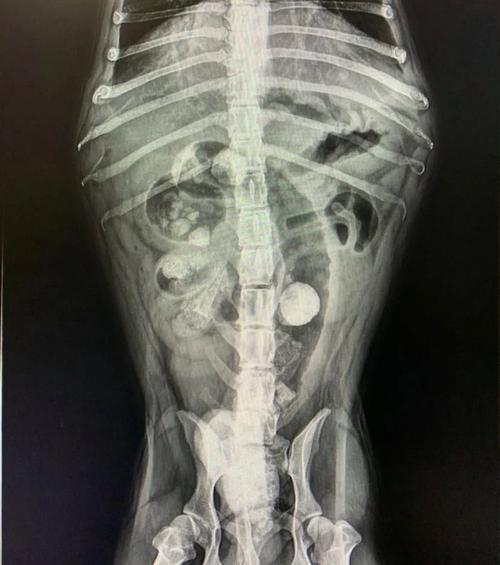

狗狗胃下面的肠子里有东西卡住怎么办?去检查拍片子医生说有东西在里面...

如果您的狗狗不慎吞食了异物,且异物卡在了肠子里,应立即前往宠物医院进行X光检查。 如果异物较小,医生可能会建议喂食一些化毛膏或者富含油脂的食物,这些有助于异物通过肠道排出。 同时,可以给狗狗喂食一些肠胃宝等益生菌,以保护肠胃健康并促进肠胃蠕动。

如果是误食了异物,卡在肠道里了,就要尽早去医院拍片检查,如果异物不大的话,可以喂些化毛膏或油脂大的食物,可以帮助异物排出,也可以把肠胃宝喂一下,能保护肠胃,促进肠胃蠕动。但如果异物较大,就只能尽早手术治疗了。

〖贰〗、以下是狗狗肠梗阻的治疗方法: 寻求兽医帮助:如果怀疑狗狗患有肠梗阻,应立即带它去兽医那里就诊。 诊断确认:兽医可能会进行体格检查、触诊和X光等检查,以确定是否为肠梗阻。根据严重程度,可能还需要进行超声波或其他进一步检查。

〖叁〗、如果你怀疑狗狗有肠梗阻,请立即采取行动。 立即就医:带狗狗去兽医诊所或紧急救治中心。专业兽医会进行体检和必要的检查,如X光或超声波,以确定肠梗阻的位置和严重程度。 不要试图自行处理:肠梗阻需要专业医生的干预和治疗。不要尝试使用家庭疗法或药物来解决问题,这可能会加重狗狗的病情。